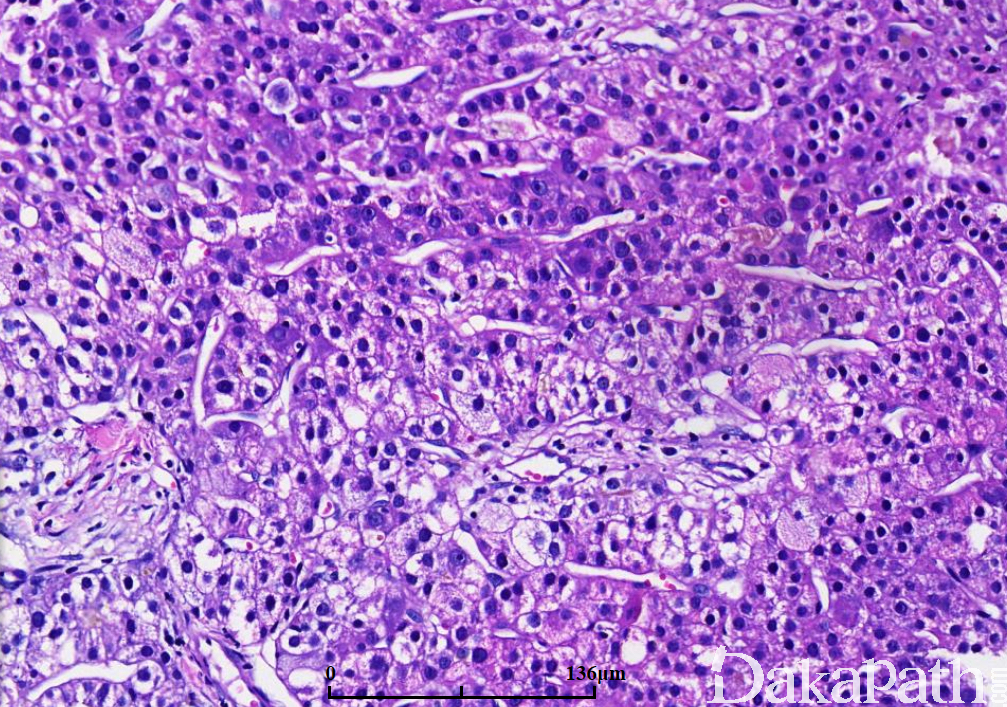

主要有三种组织结构,梁状、腺泡状和实体型:

a)梁状结构由 3 层以上细胞组成,周围围绕扁平内皮细胞,无 kupffer 细胞;

b)腺泡结构由实心细胞巢中央区域退变形成假腺样结构,腔内为胶样物,也可以由扩张的胆管形成腺样结构;

肿瘤细胞常类似肝细胞,通常体积较大,多角形,核空泡状,位于中央,可有核仁;

间质为毛细血管化的肝窦,被覆扁平内皮细胞,CD34 染色阳性;

a)高分化:体积一般较小,肝细胞索不超过 3 层细胞,细胞比正常肝细胞小,核异型轻微,细胞密度相当于正常肝脏的 2 倍,但网状纤维支架紊乱,可有假腺样结构,脂肪变性常见;

b)中分化:肝细胞索宽度 4 个细胞以上,细胞体积较正常肝细胞大,胞质嗜酸性,核仁突出,可见假腺样结构和瘤巨细胞;